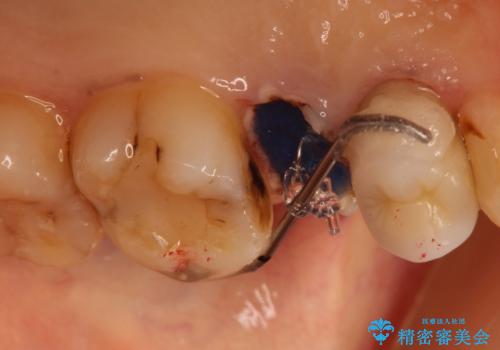

かぶせ物と詰めてある修復物を除去すると歯肉の中まで虫歯になっていました。

歯を部分矯正で引き上げて、虫歯を徹底的に取り除き、適合の良いかぶせ物を装着する計画としました。